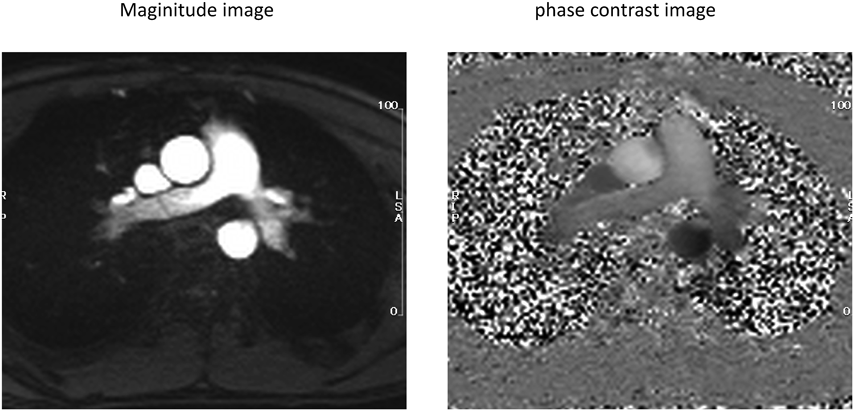

2D-PC法の撮影ではFig. 1に示すように,Magnitude画像とPC画像の2つの画像が得られる.Magnitude画像は,心臓や血管などの構造物特性(質)を信号強度(明るさ)の強弱で表現したcine画像である.一方,Phase Contrast画像は双極性のVelocity encoding gradientを用いて,血液の動きをCMR信号の位相情報に変換して描出した画像である.PC画像の信号強度は血流速度に対応する位相−πからπまでの値で表される.この撮影方法では血液の動きは単一の方向に限定され,その方向にVelocity encoding gradientが適用される.

Fig. 1 2D-PC CMR image set

流量を計測したい血管の長軸2方向の断面画像から,血管に直交する断面を設定し撮影する.撮影条件や断面の設定については41),浦邊らの報告を参照されたい42).任意断面の信号強度を反映した動画(Magnitude画像:Fig. 1左)と血流速度を反映した位相差画像の動画(Phase Contrast画像:Fig. 1右)がセットで得られる.ソフトウェアを用いて個々の血管・弁口を断面上で囲う(ROI: Region of interestの設定)ことで,このROI部分を通過する1心拍分の血流量が順行性,逆行性,差し引きの量として計算・定量される(Fig. 3左下).我々の標準プロトコールでは原則10断面の撮影から11箇所の血流を計測し,この方式をFLOW-11と称している(Fig. 520, 43).上行大動脈(AAo),主肺動脈(MPA),上大静脈(SVC),下大静脈(IVC)(+下行大動脈(DAo)),左右肺動脈(LPA, RPA),左右肺静脈(LPV, RPV),僧帽弁(MV),三尖弁(TV)の11箇所である.疾患によってはアレンジすることもあるが,この10断面が撮影できていれば,一部不明瞭であっても基本的な血行動態を導くことが可能である20)